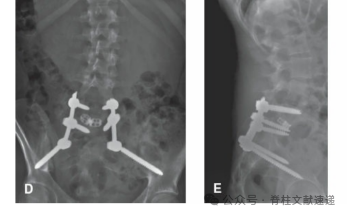

术后影像资料

原位融合较复位技术简单,核心理念是从S1穿螺钉通过骶骨岬到达L5椎体实现固定。操作和前面一样,显露、置钉、减压(若患者存在神经症状),采用L4椎弓根螺钉、S1螺钉从骶骨岬打入L5椎体进行串联固定(连续透视或导航下),S2AI或髂骨螺钉固定,后外侧植骨融合。如下图。该技术最大的问题是不融合率较高,越20%。部分患者腰椎滑脱会继续进展,而在此手术的难度更大,风险更高。